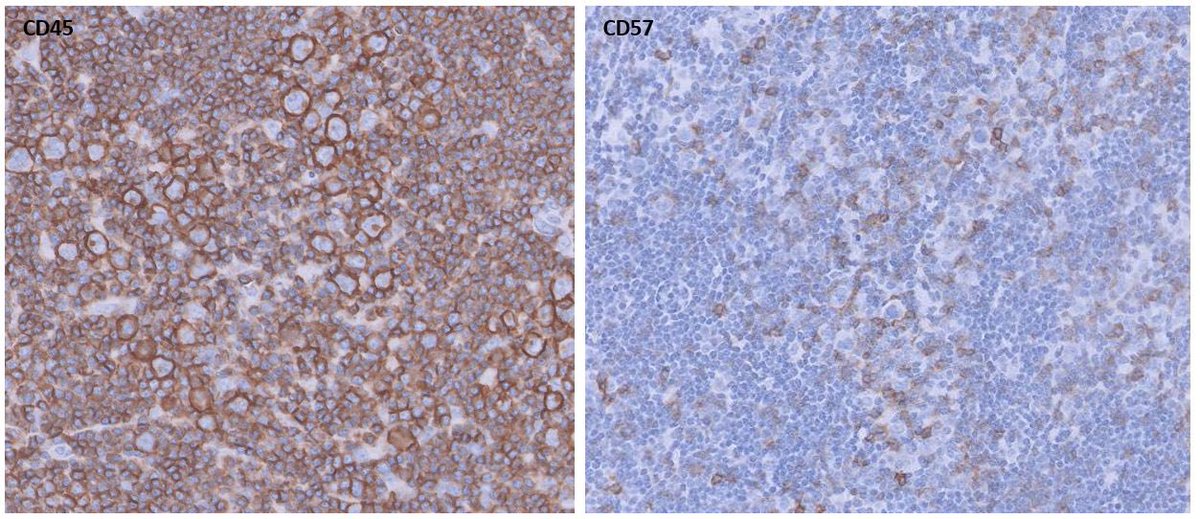

Pre-auricular nodule x 1month from 31yo patient, no other complaint. #pathtwitter #surgpath #ENTpath #hemepath #pathboards Einstein Montefiore Pathology Ridin Balakrishnan, MD Hansini Laharwani Siba El Hussein, MD Mitul B. Modi, MD Tristan Rutland MBBS FRCPA IFCAP Jerad Gardner, MD Kamran Mirza MD PhD - کامران مرزا

63/male with abdominal lymphadenopathy. DQ gave the initial clue to hemepath diagnosis. Positive CD3/5/7/25. CD30 diffuse, ALK1/CD20 negative. CD30+ Mature T-cell lymphoma. D/D ALCL or ATLL HTLV1 is positive! #cyto #hemepath #PathTwitter Kevin Kuan Yanhua Wang #bridgingcytoheme